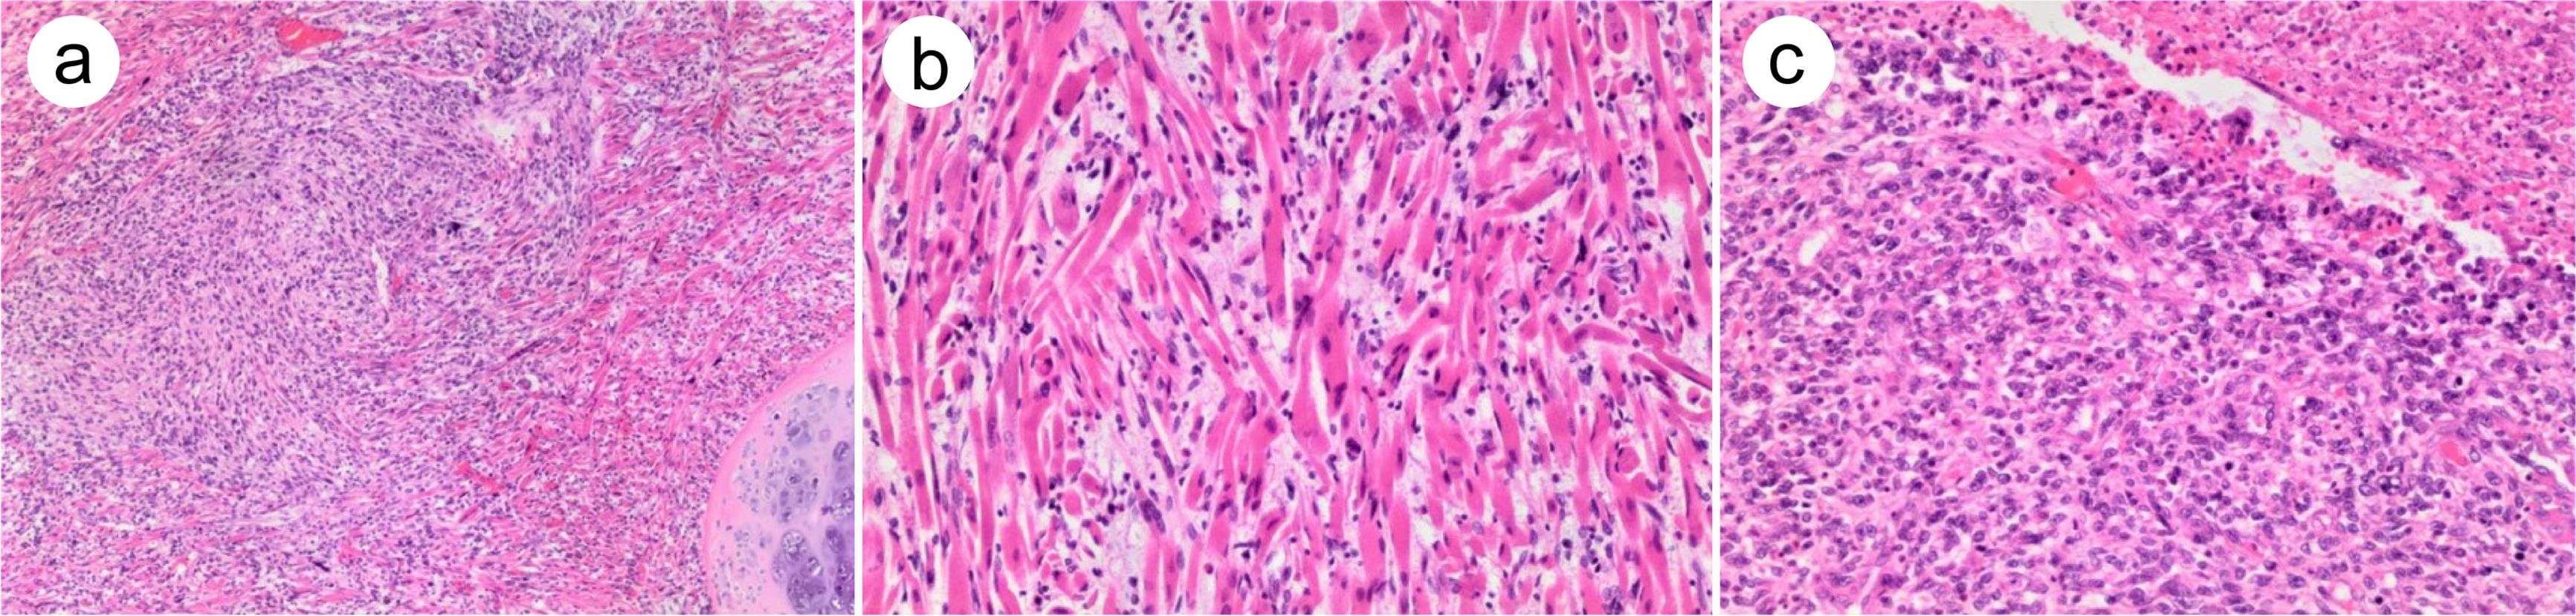

As a pluripotential tissue, teratoma can potentially undergo malignant transformation along different elements of the embryo.29 ENT, previously called primitive neuroectodermal tumor, may result from malignant transformation along the mesodermal lines. Patients with ENT of SM are often classified as having a central nervous system-type primitive neuroectodermal tumor due to the lack of recurrent chromosomal translocation, t(11;22)(q24;q12).30 The primitive ENT component typically shows small, round, blue malignant cells in diffuse sheets (Fig. 4a). They occasionally form tubules or pseudorosettes. These tumor cells have indistinct cytoplasmic membranes, a scant clear to eosinophilic cytoplasm, and finely stippled chromatin with inconspicuous nucleoli (Fig. 4b). Mitotic figures and apoptotic bodies are frequent. There may be a basement membrane that separates the tubules from the adjacent stroma. Other growth patterns, such as medulloblastoma/supratentorial, neuroblastic tumor with abundant neuropil and true rosettes, and small cell embryonal tumor (Ewing sarcoma-like), also have been reported.

Fig. 4  Embryonic-type neuroectodermal tumor arising from a testicular germ cell tumor.

(a) Overgrowth of small, blue, round malignant cells in a sheet-like growth pattern. Note the adjacent testicular parenchyma in the left upper corner. (b) High-power view of the tumor showing uniform small round cells with round/oval nuclei, finely stippled chromatin, inconspicuous nucleoli, scant clear-to-eosinophilic cytoplasm, and indistinct cytoplasmic membranes. Pseudorosettes (arrow) can be seen. (c) The tumor cells are strongly positive for CD99.

As for the immunohistochemistry studies, CD99 (Fig. 4c) and SOX11 are considered the most sensitive markers of undifferentiated ENT, with strongly diffuse positive staining.31,32 Undifferentiated ENT also expresses synaptophysin, chromogranin A, and cytokeratin. As glial differentiation markers, glial fibrillary acidic protein and S100 are typically negative in the undifferentiated ENT components, although they are positive in the differentiated ENT components.32